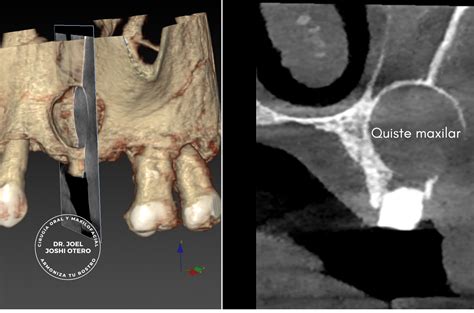

En la ortopantomografía (radiografía en 2D de toda la boca) el quiste maxilar se observa como una zona oscura y redondeada en forma de bolsa. Algunos quistes tienen una causa genética. Entre ellos están los relacionados con el desarrollo de los maxilares y los dientes en edades tempranas. Otros quistes derivan de caries profundas que han llegado al nervio.

En la imagen de la portada (corte de un TAC en 3D) se observa un quiste naso-palatino, uno de los más comunes de la cavidad oral.